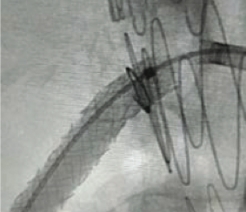

FEVAR

Stent protruding into aorta

Post-dilatation with FLASH

TRUE 360° result